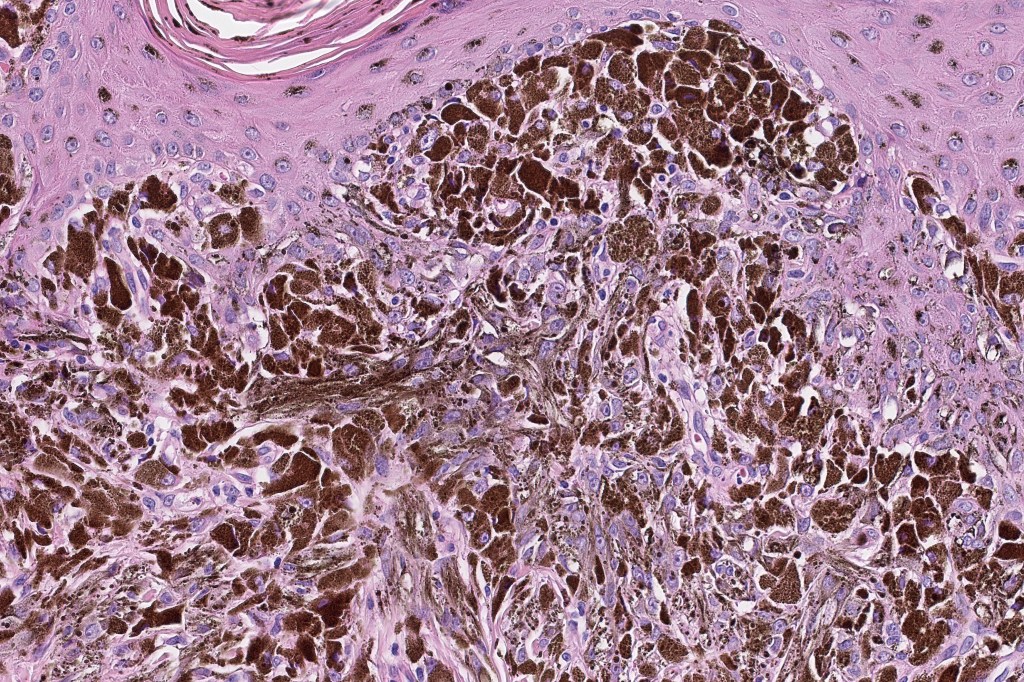

•Composed of an admixture of large epithelioid melanocytes with vesicular nuclei containing a very prominent nucleolus (fried egg cells), spindle cells, dendritic cells & melanophages

•The epithelioid cells are typically very uniform

•Few mitoses

•Perineural infiltration sometimes evident

•Absent necrosis & lymphovascular invasion